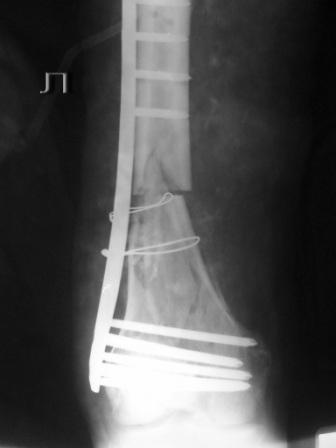

Пациенту 50 лет. 24.11.09 сделали л\бедро.

Имя     : PB254033.jpg